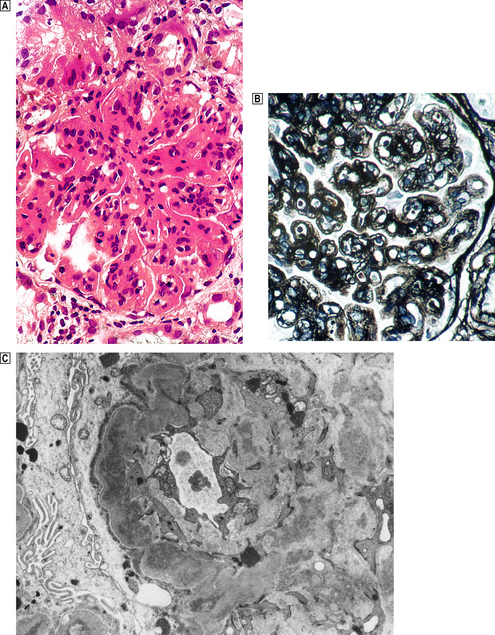

Membrano-proliferative glomerulonephritis

Membrano-proliferative glomerulonephritis (MPGN), a glomerular lesion with many causes, features both membrane thickening and proliferation (Fig. 21.8A). In addition, there is accentuation of the lobular architecture of the glomerulus. The thickened capillary walls, which have a duplicated ‘tram track’ appearance of the basement membrane revealed by silver staining (Fig. 21.8B), prompt the alternative name of mesangiocapillary glomerulonephritis (MCGN). This duplication is due to a new layer of basement membrane laid down by cell processes interposed between the endothelium and the basement membrane (Fig. 21.8C). Two main types are recognised.

image

Fig. 21.8 Membrano-proliferative glomerulonephritis. image The combination of mesangial cell proliferation and basement membrane thickening exaggerates the lobular architecture of the glomerulus. image MST stain shows the new layer of basement membrane giving rise to the reduplicated peripheral profiles characteristic of mesangiocapillary glomerulonephritis. image Electron microscopy shows the wall between the capillary lumen and urinary space to be thickened by the interposition of cellular processes and electron-dense deposits in relation to them.

Type I MPGN

Type I MPGN is an immune complex-mediated lesion. Patients with this condition fall into two groups:

those with mixed cryoglobulinaemia—c. 80% have hepatitis C

those without cryoglobulinaemia, occurring in a wide range of conditions including infections, tumours, collagen vascular diseases, hereditary and acquired complement deficiencies, drug reactions and genetic disorders (e.g. sickle cell disease).

Most patients present with nephrotic syndrome, but some have haematuria. A persistently low serum complement C3 (hypocomplementaemia) occurs in two-thirds of patients. There is progressive deterioration over 10 or more years.

Type II MPGN

Type II MPGN is characterised by markedly thickened capillary walls expanded by a discontinuous linear deposition of altered basement membrane material and C3. Ultrastructurally, large electron-dense ribbon-like deposits give rise to the preferable alternative name—dense deposit disease (Fig. 21.9).

Fig. 21.9 Dense deposit disease. Electron micrograph showing the irregular ribbon-like deposits in dense deposit disease.

The lesion results from self-perpetuating activation of the alternative pathway of the complement cascade by a C3 nephritic factor (C3NeF), now termed NeFa, and explains the hypocomplementaemia.